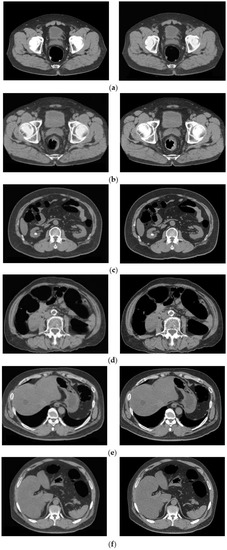

3.1. Cleansing Images Generated Using CycleGAN